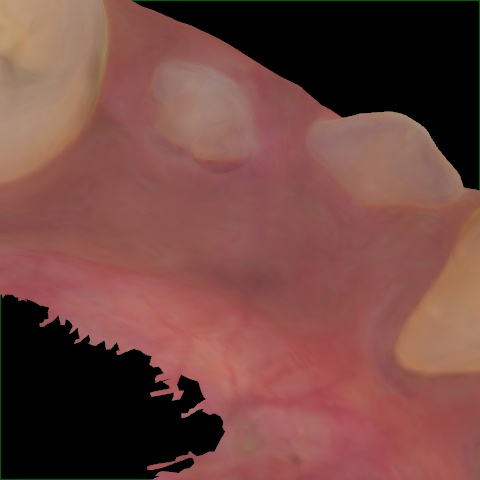

NHD25470

Annotated as "Good"